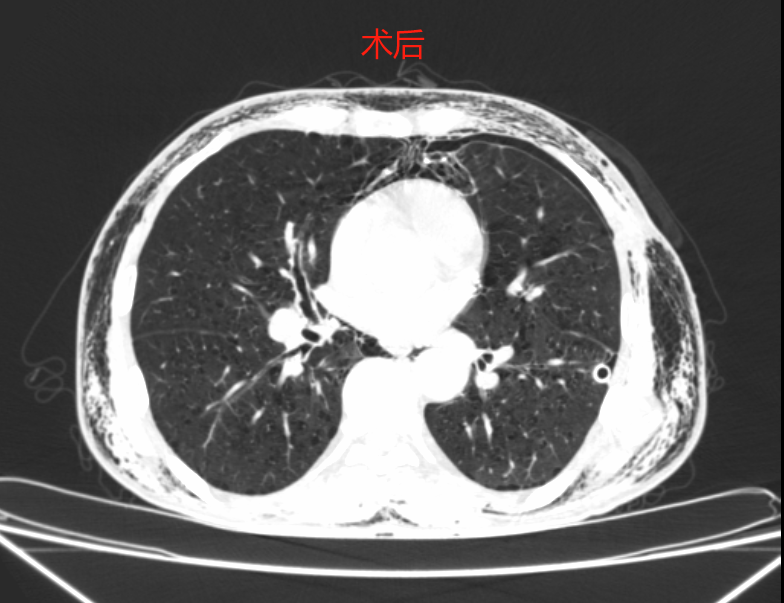

術(shù)后,陳大叔安全返回病房,術(shù)后第2天,攜引流瓶自如行走,復(fù)查影像資料提示肺組織復(fù)張良好,達到預(yù)期治療效果?,F(xiàn)已康復(fù)出院。